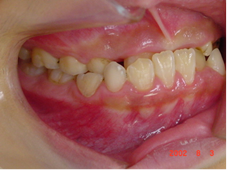

前回、低位咬合の出っ歯の症例を説明しましたが、今回は低位咬合で受け口の症例を説明していきます。

低位咬合で受け口の場合は、特に上顎骨の成長に影響を与えます。

上顎骨は下顎骨と成長の仕方が異なり、誕生から10歳位まで成長し、そこで成長が止まります。

そのため、出っ歯の低位咬合以上に早期治療の必要性が高まります。